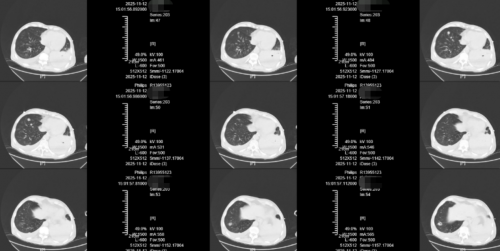

治疗后的胸部CT(11月12日):双肺散在炎症较11.7日有减轻,双肺炎症明显吸收。

抗细菌、抗病毒和抗炎的综合策略是救治成功的核心。根据NGS结果,选择哌拉西林他唑巴坦4.5 g,每8小时一次,覆盖肺炎克雷伯菌及屎肠球菌。联合支气管镜吸痰及肺泡灌洗,有效清除病原菌及痰液,降低细菌负荷。患者入院后立即给予奥司他韦75 mg,每12小时一次。尽管已超过48小时理想用药窗口,但研究表明,对于重症或高危人群,延长奥司他韦疗程仍可抑制病毒复制,减少病毒载量,降低继发细菌感染风险。入院后即给予西维来司他钠0.32 g(4.8 mg/kg)静脉滴注,每日一次,疗程7天。西维来司他钠为中性粒细胞弹性蛋白酶抑制剂,本例患者应用西维来司他钠5天时,复查肺部CT示双肺炎症明显吸收,氧合显著改善,成功脱机拔管,提示抗炎治疗在遏制炎症风暴、改善肺病理损伤方面发挥了重要作用。